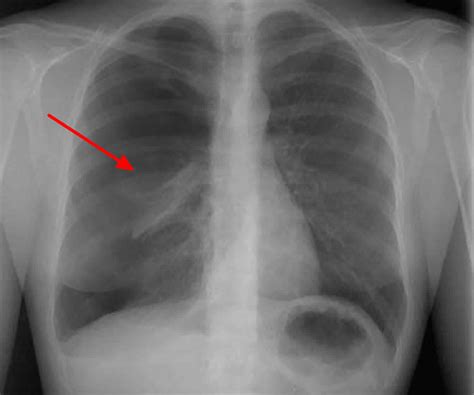

So, you’re wondering, “How will I know if I or someone I know is experiencing a pneumothorax outlet ?” That’s a super important question, guys, because recognizing the symptoms early can make a world of difference in getting prompt treatment. The classic symptom, and often the first one people notice, is sudden, sharp chest pain. It can feel like a stabbing pain, and it often gets worse when you take a deep breath, cough, or even sneeze. Imagine that! It’s like your chest is screaming at you to stop moving. Another major sign is shortness of breath, or what doctors call dyspnea. You might feel like you can’t catch your breath, or you’re breathing really rapidly and shallowly. This can range from mild discomfort to severe difficulty breathing, depending on how much your lung has collapsed. Some people might also experience a feeling of tightness in their chest. If the pneumothorax is larger, or if it’s progressing to a tension pneumothorax (which, as we mentioned, is a serious emergency), you might notice other worrying signs. These can include a rapid heart rate (tachycardia), bluish discoloration of the skin and lips (cyanosis) due to lack of oxygen, dizziness, and even fainting or loss of consciousness. In some cases, especially with a smaller, spontaneous pneumothorax, the symptoms might be milder and might even resolve on their own. But guys, don’t ever assume it’s nothing! It’s always best to get checked out by a medical professional if you have any concerns. A doctor will typically listen to your chest with a stethoscope and might hear decreased or absent breath sounds on the affected side. They’ll likely order imaging tests, like a chest X-ray, which is usually the go-to diagnostic tool for confirming a pneumothorax. Sometimes, a CT scan might be needed for a more detailed view. The key takeaway here is to pay attention to your body. Sudden chest pain and difficulty breathing are not things to brush off. They are your body’s way of telling you something is wrong, and it’s time to seek medical help.